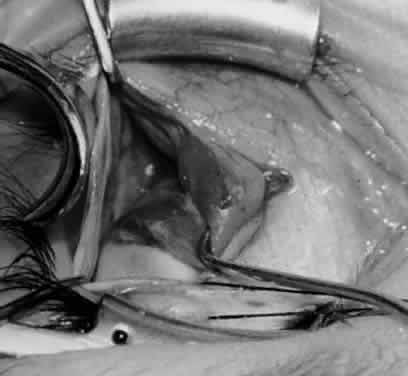

Fig. 3. The eye is retracted superonasally with the 4-0 silk traction suture. The suture is attached to the drapes with a hemostat. A Stevens hook is placed along the inferior border of the lateral rectus muscle and drawn temporally. A von Graefe hook is placed within the incision and drawn inferotemporally to expose the inferior oblique muscle.

Fig. 4. A stiff iris repositor can be placed against the sclera to depress the sclera and enhance the view of the inferior oblique muscle. The inferior temporal vortex vein adjacent to the Stevens hook is retracting tissue along the inferior border of the lateral rectus muscle. The second Stevens hook is pointing to the inferior oblique muscle.